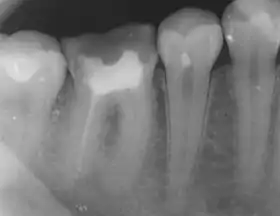

Apical periodontitis is typically the body's defense response to the threat of microbial invasion from the root canal.[1] Primary among the members of the host defense mechanism is the polymorphonuclear leukocyte, otherwise known as the neutrophil. The task of the neutrophil is to locate and destroy microbes that intrude into the body – anywhere in the body – and they represent the hallmark of acute inflammation.[2]

The body's response to microbial invasion